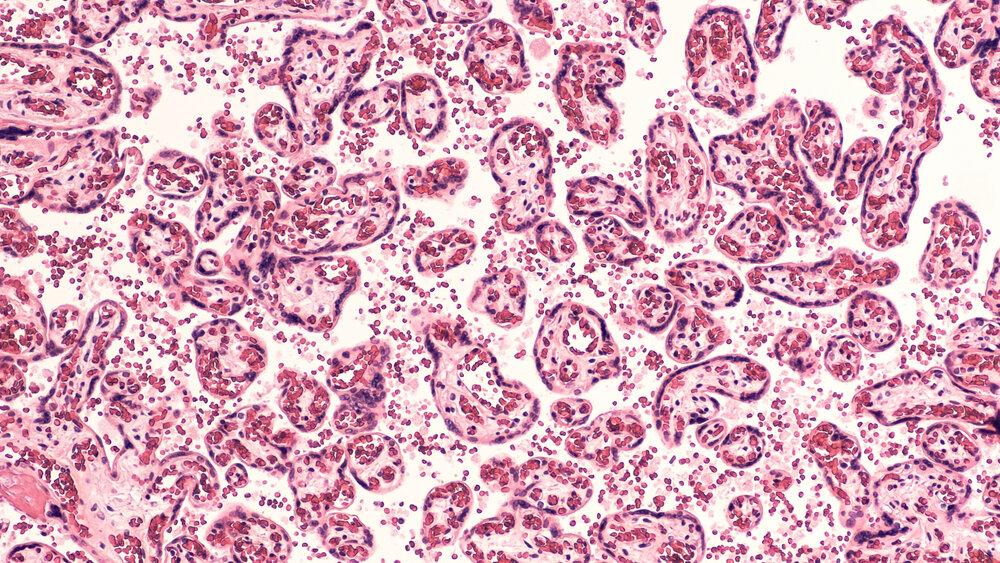

Исследователи из детской больницы UPMC в Питтсбурге обнаружили, что инфузия пуповинной крови — легко доступного источника стволовых клеток — безопасно и эффективно пролечила 44 ребенка, рожденных с различными незлокачественными генетическими нарушениями, включая серповидноклеточную анемию, талассемию, синдром Хантера, болезнь Краббе, метахроматическую лейкодистрофию и целый ряд иммунодефицитов. Это самое большое испытание в своем роде на сегодняшний день. Идея заключалась в том, чтобы создать достаточно универсальное лечение, а не искать индивидуальную терапию для всех этих редких заболеваний, и сделать это с минимальным риском для пациентов. Результаты опубликованы в Blood Advances. По словам автора исследований, доктора медицинских наук, директор отдела трансплантации костного мозга и клеточной терапии в детской больнице UPMC, крутые технологии — это хорошо, но они недоступны. Переливание пуповинной крови в этом плане более надежный, простой и дешевый метод. Для этого исследования

Исследователи из детской больницы UPMC в Питтсбурге обнаружили, что инфузия пуповинной крови — легко доступного источника стволовых клеток — безопасно и эффективно пролечила 44 ребенка, рожденных с различными незлокачественными генетическими нарушениями, включая серповидноклеточную анемию, талассемию, синдром Хантера, болезнь Краббе, метахроматическую лейкодистрофию и целый ряд иммунодефицитов. Это самое большое испытание в своем роде на сегодняшний день.

Для этого исследования участники получили внутривенные инъекции пуповинной крови, которая была взята из пуповины и плаценты здоровых детей сразу после рождения и была заморожена до момента применения.

Чтобы «освободить место» в костном мозге для того, чтобы донорские стволовые клетки могли укорениться и чтобы можно было предотвратить их отторжение, участники исследования получили низкие дозы химиотерапии и иммунодепрессантов. Как только клетки интегрировались в тела пациентов, эти препараты были отменены. Чтобы вернуть иммунную систему в рабочее состояние, исследователи оставили небольшую долю пуповинной крови и дали ее участникам через несколько недель после первоначального вливания.

Исследователи проспективно оценили новую схему RIC для лечения с алемтузумабом, гидроксимочевиной, флударабином, мелфаланом и тиотепой с применением единственного блока UCB в 44 последовательных пациентах с врожденными генетическими заболеваниями обмена веществ, иммунитета или гематопоэза (кроветворения). Кроме того, 5% трансплантата UCB повторно криоконсервировали и зарезервировали для посттрансплантационной инфузии лейкоцитов донора пуповины. Все пациенты имели хороший результат в среднем через 15 дней после трансплантации, и химеризм был> 90% донором у большинства пациентов через 1 год после трансплантации только с одной вторичной недостаточностью трансплантата. Заболеваемость трансплантатом против хозяина II-IV степени (GVHD) составила 27% без обширных хронических поражений. Общая выживаемость составила 95% (95% ДИ, 83-99) и 85% (95% ДИ, 64-93) через 1 и 5 лет после пересадки, соответственно. Никакой существенной токсичности для конечных органов не наблюдалось. Эта схема трансплантации RIC с использованием единственного трансплантата UCB привела к выдающейся выживаемости и удивительно низким показателям отказа трансплантата. Реализация протокола, не требующего фармакокинетического мониторинга, была бы возможной и применимой во всем мире для детей с наследственными нарушениями обмена веществ, иммунитета или гематопоэза (кроветворения).